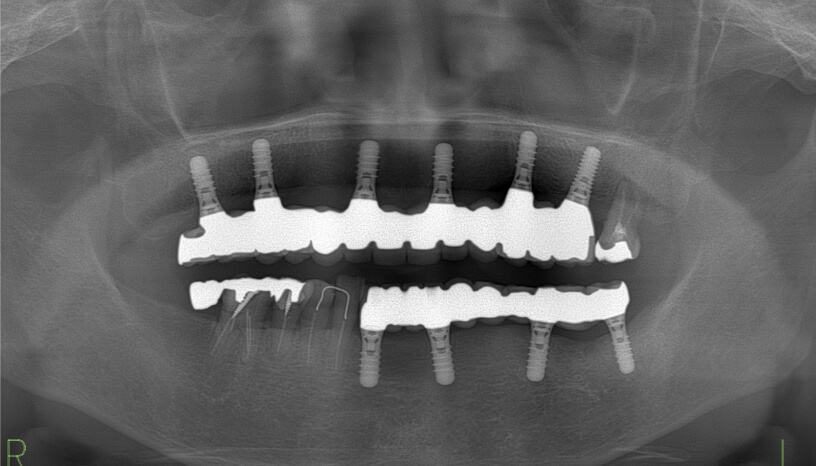

安全で正確な診断のための最新型CTを導入しています。CTというのは骨の状態を三次元で検査できる最新設備です。顎骨には神経や血管が通っていて、安全に治療を行うには不可欠な設備です。日本の歯科医院でCTを常備している医院は10%未満と言われていますが、インプラントを頻繁に行っている医院では確実に保有している設備です。最初のカウンセリングから終了後までいつでも撮影が可能です。

• レントゲン写真

画像が鮮明なため、的確な診断ができます。

3次元で診断できるため、安全性が高くリスクの少ない治療が行えます。